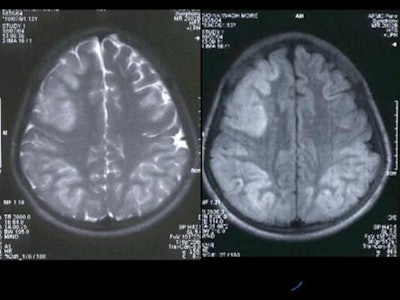

MRI was performed with the following sequences: TSE and gradient-echo T2 and FLAIR axial, TSE T2 sagittal and coronal, 3D Turboflash T1 sagittal with multiplanar reconstructions, and diffusion-weighted images with b-values of 500 and 1000 s/sq mm.

There was symmetrical hyperintensity at both putamina and thalami and the head of both caudate nuclei on T2WI and FLAIR images [Figure 1 and 2]. The thalamic lesions appear hypointense on T1WI while the putaminal lesions show mixed signal with magnetic susceptibility effects on gradient-echo images.